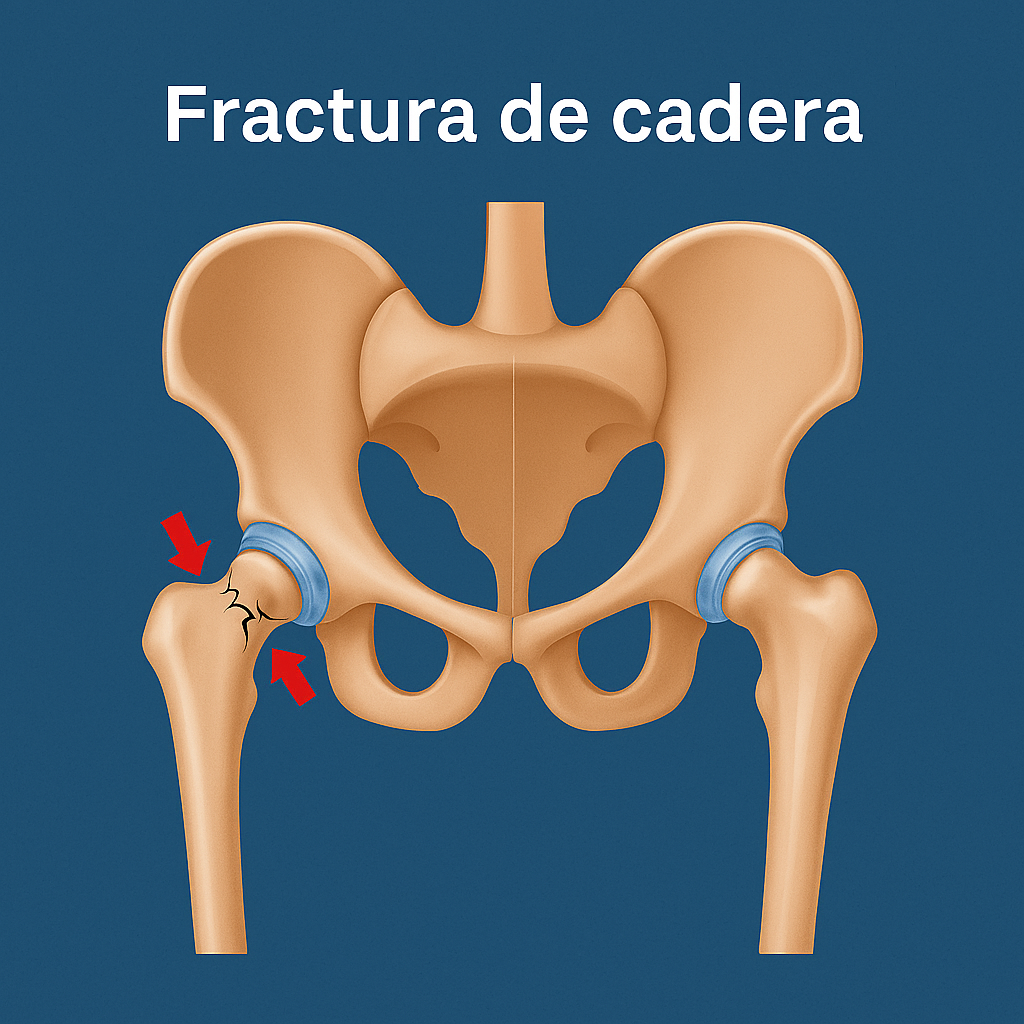

Fracturas de Cadera

¿Qué es?

Rotura del hueso femoral cerca de la articulación de la cadera, frecuente en adultos mayores por caídas o en jóvenes por traumatismos.

Síntomas:

- Dolor intenso e incapacidad para caminar

- Deformidad o acortamiento de la pierna

- Inflamación y hematoma -

Tratamiento:

- Cirugía de fijación o reemplazo articular

- Rehabilitación postoperatoria

- Prevención de futuras caídas y fortalecimiento óseo